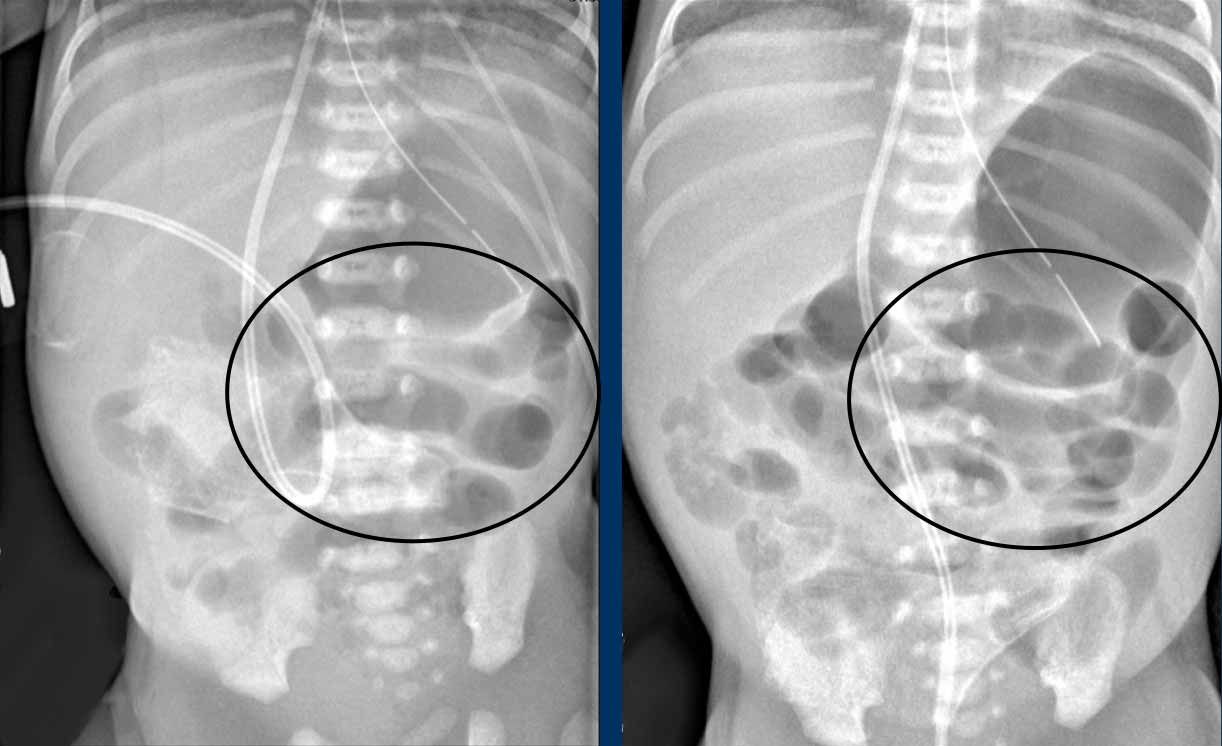

Hình ảnh

Hai phim X-quang chụp cách nhau vài giờ cho thấy ở vùng bụng trên chỉ có các quai ruột giãn nhẹ nhưng không có nếp niêm mạc, không thay đổi theo thời gian. Đây là dấu hiệu của vắng mặt nhu động ruột.

Lịch chụp lại được khuyến cáo là mỗi 6-8 giờ, nhưng tất nhiên phụ thuộc vào tình trạng lâm sàng.

Một ví dụ khác về quai ruột cố định.

Cuộn qua các hình ảnh.